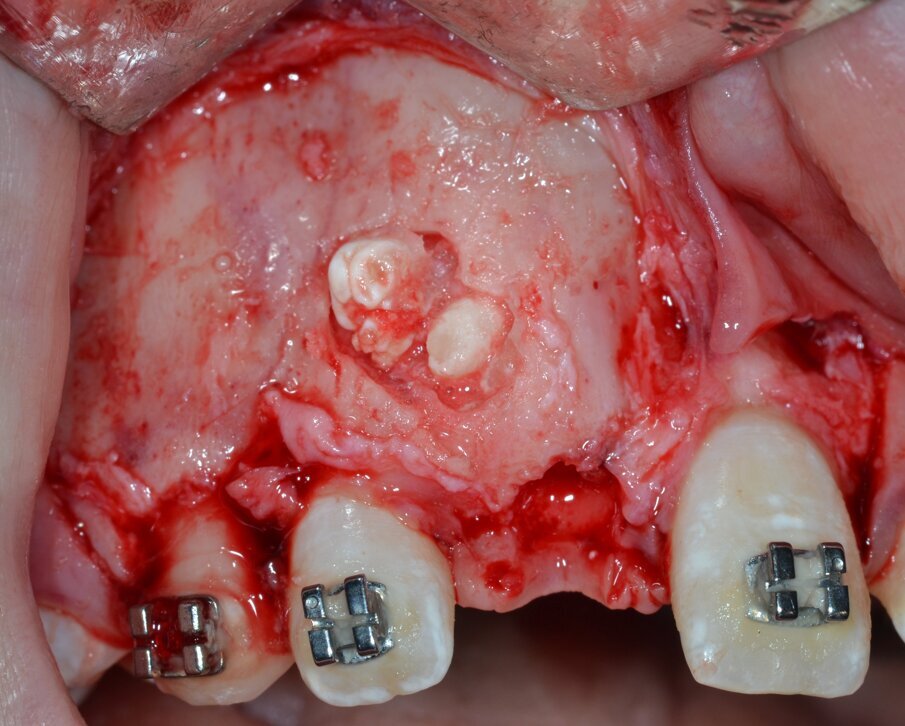

Una volta esposta e isolata la massa, in accordo con le indagini radiografiche di 1° e 2° livello preventivamente eseguite, l’aspetto intraoperatorio conferma la diagnosi di odontoma composto, caratterizzato clinicamente dalla presenza di numerosi denticoli immersi in uno stroma di tipo fibroso (Fig. 8).

Fig. 8_Esposizione e isolamento della neoformazione.